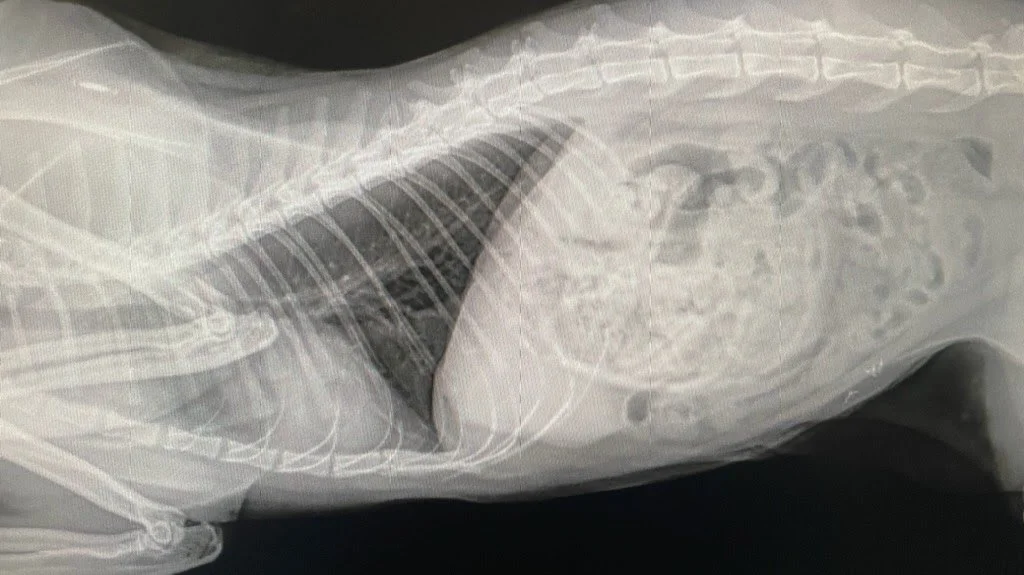

Foreign Body Obstruction

Gastrotomy - an incision into the stomach to remove obstructive material.

• Enterotomy - an incision into the intestines to remove obstructive material.

• Resection and anastomosis - the removal of non-vital intestines. This can occur when the obstructive material blocks blood flow to that section of the intestines.

Pricing: $1800-3000

(Base price includes an exploratory laparotomy - price is dependent if single incision or multiple incisions with surgical removal of intestines)

X-ray image of a small animal, possibly a cat or small dog, showing rib cage, spine, and internal organs.